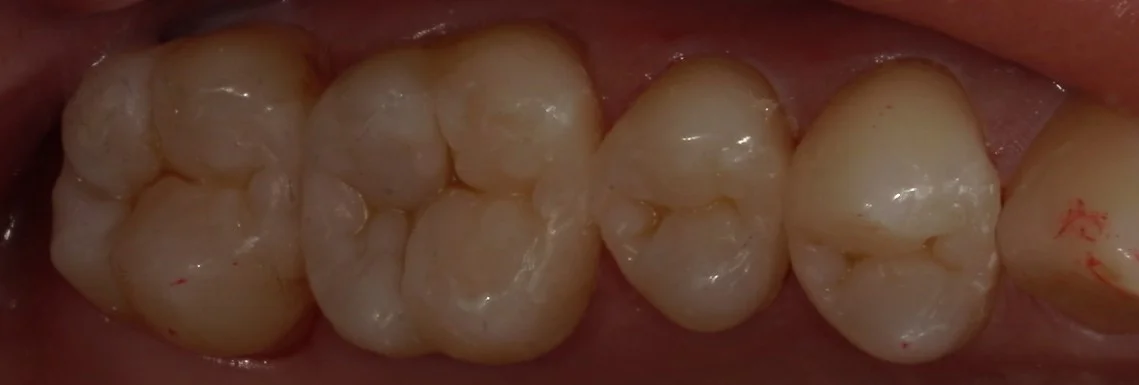

さて、詰め終わったのがこちらになります。

全体的に金属を白い詰め物に。|坂寄歯科医院(取手市藤代) - 画像4

違和感なく綺麗に詰められたかと思いますヽ(゚∀゚)ノ パッ☆

左から2番目が非常に大きかったので、今後痛みが出ないことを祈るだけですね・・・。

患者さんからは「歯が新品になったみたい!」って言って喜んでいただけました。

今回は遠方からの方なので、纏めて4本一気にやっていますが、基本的には疲れすぎるので2本ずつ行うことが多いです(;・∀・)